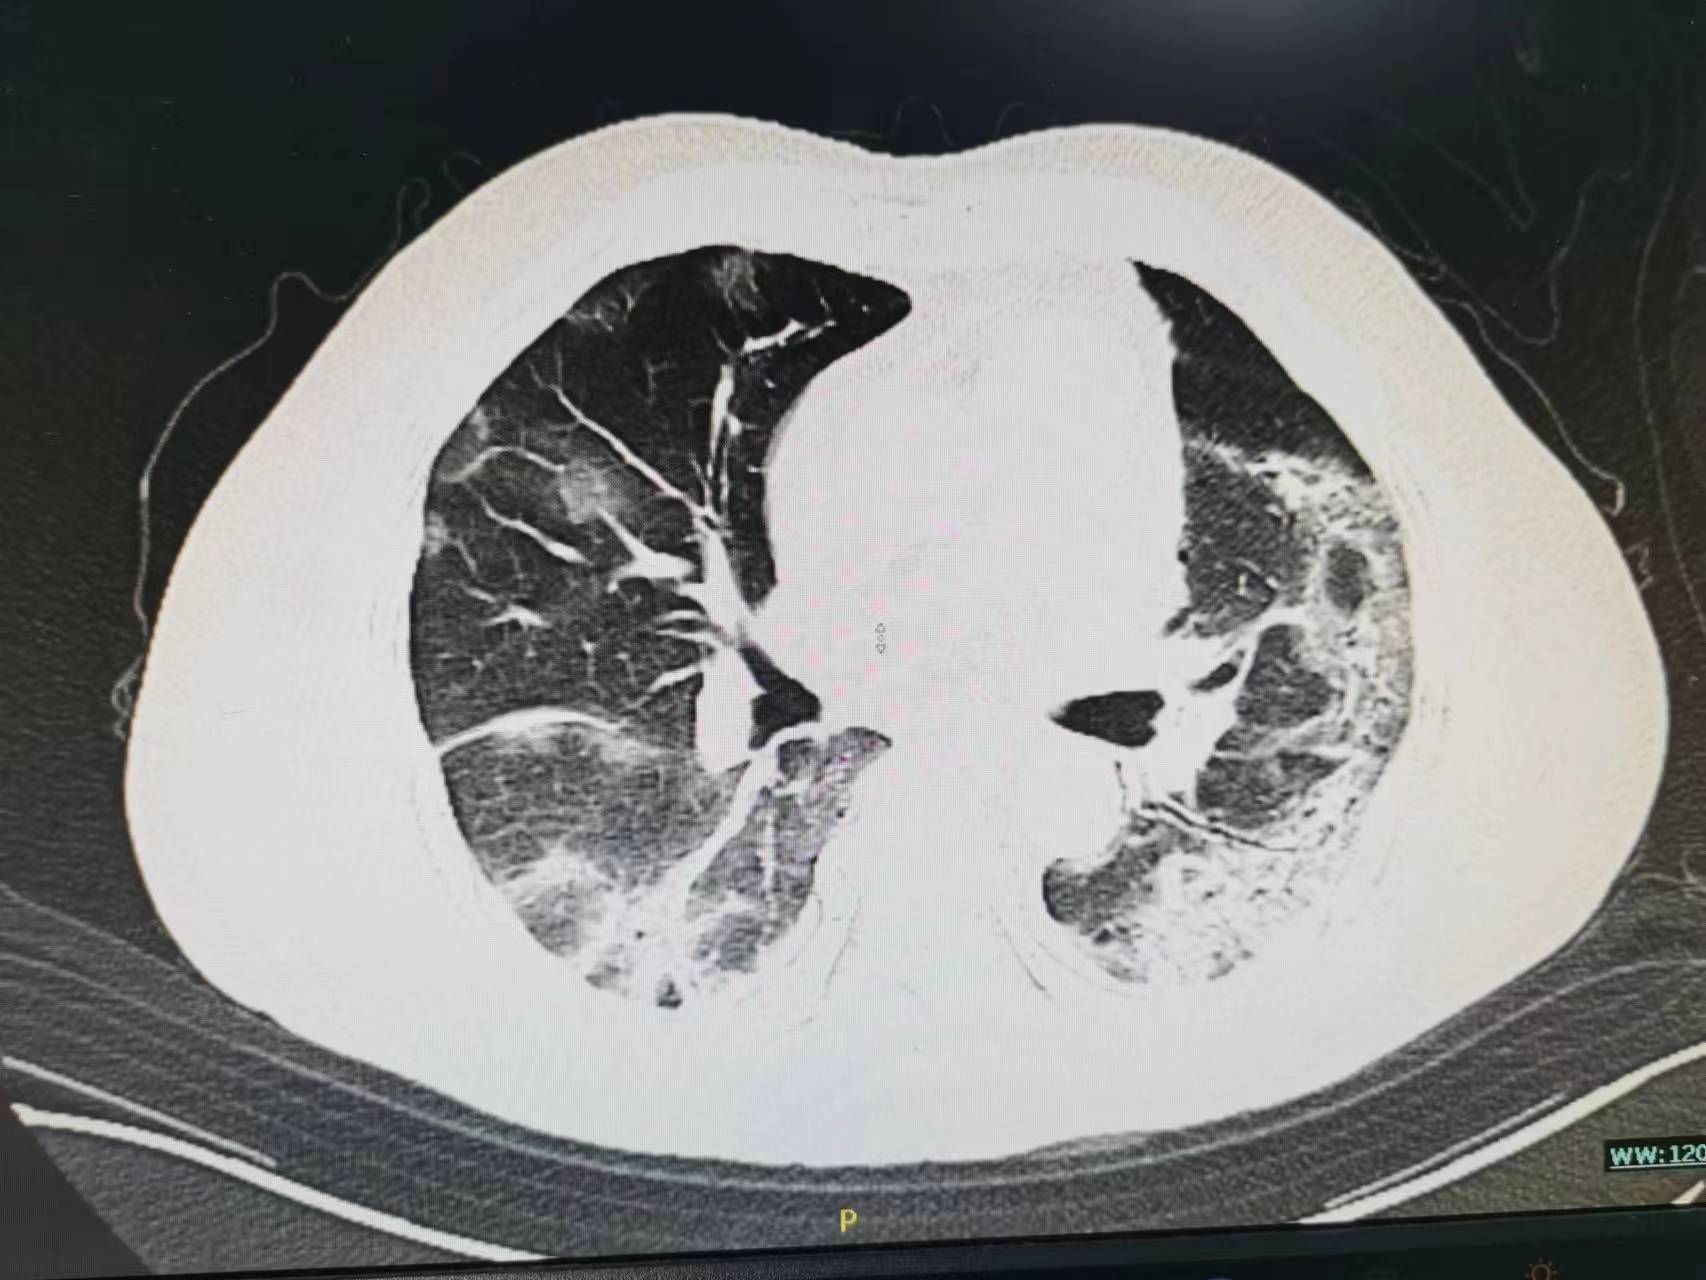

开始家属接受不了,找关系送老太太来医院是为了打“点滴”的,你给我说这个合适吗?病人的情况真有这么重吗?现在老太太不是好好的吗?于是再次向家属讲解病情,重点讲述了病人病情可能的发展并告知可能需要呼吸机,家属还是觉的不可能,查了胸部CT之后才发现病情已如此严重了,基本白肺了。这时候老太太才说这几天感觉到有点“憋的慌”,只是限于不想麻烦孩子的关系不想说,觉的忍忍就过去了。最后还是拗不过家属的要求才来医院的。

老年人阳后长期低热,肺部感染